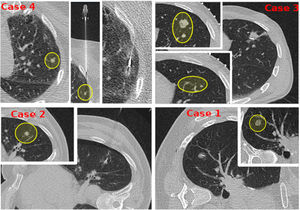

Case based discussionIn order to explain different technical variations, and better expose M-GOLL's potential usage, we present four different cases (Fig. 1).

Case#1: 62yo female patient, 2 years disease free after a right-upper lobectomy for a T3N0M0 adenocarcinoma, suspicious for relapse for a 12mm sub-solid pulmonary nodule on the right lower lobe.

Case#2: 57yo male patient with a 13mm lung colon metastasis on the 6th left segment, at 2cm from the chest-wall.

Case#3: A 53yo male with a previous SIVATS right lower lobectomy for a T3N0M0 adenocarcinoma, was diagnosed of pulmonary nodules on the left upper lobe. CT-guided core-needle biopsy reported lung cancer relapse and showed 2 more nearby micro-nodules of 5.17 and 5.68 millimeters, located at 3cm from the chest wall.

Case#4: A 72yo female with bilateral pulmonary metastases. One of them was subsolid, with a size of 5mm on the left-upper lobe, located at 1.5cm from the chest wall.